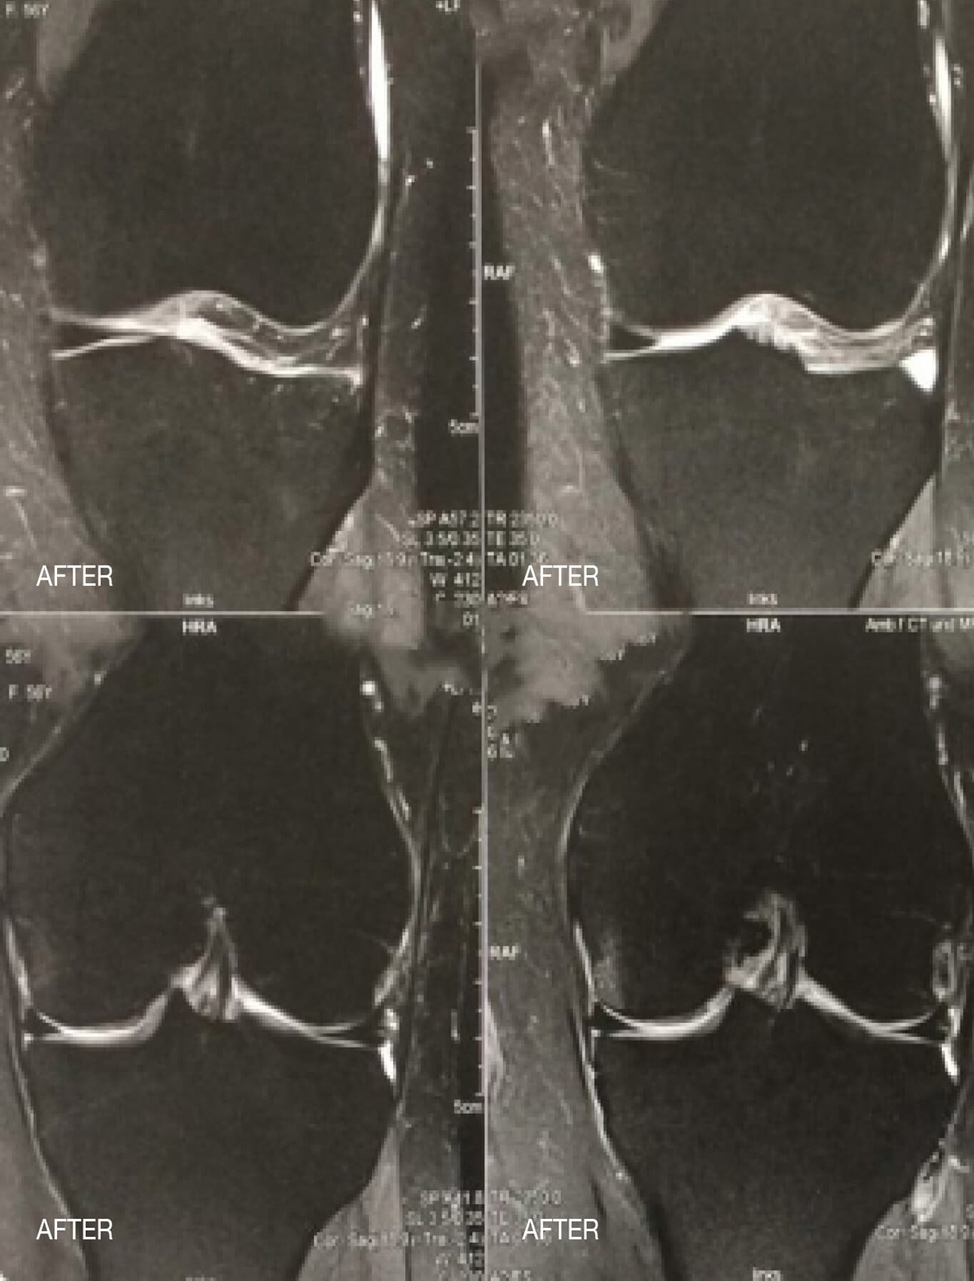

Las siguientes imágenes muestran un edema medular en la articulación de la rodilla antes y después de la terapia papimi. El tratamiento tuvo éxito tras sólo 10 sesiones.